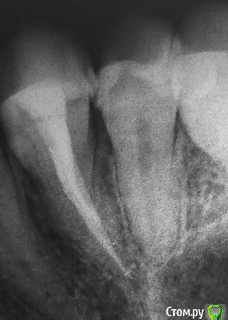

red_butler Опубликовано 10 октября, 2019 Поделиться Опубликовано 10 октября, 2019 Четвертый пролечен достойно, дискомфорт при постукивании должен пройти. Зуб обязательно восстановите искусственной коронкой. Пятый, доктор оставил часть старой пломбы? По рентгену необходимости лечения каналов не увидел. По снимку есть вопросы по контактным пунктам между пятым и шестым - пломбировочный материал в межзубном промежутке, на шестом, его нужно убрать. Если боли в пятом быстро проходящие, и не исчезнут, то ставить вопрос о повторном лечении Ссылка на комментарий

Olga2396 Опубликовано 10 октября, 2019 Автор Поделиться Опубликовано 10 октября, 2019 (изменено) Четвертый пролечен достойно, дискомфорт при постукивании должен пройти. Зуб обязательно восстановите искусственной коронкой. Пятый, доктор оставил часть старой пломбы? По рентгену необходимости лечения каналов не увидел. По снимку есть вопросы по контактным пунктам между пятым и шестым - пломбировочный материал в межзубном промежутке, на шестом, его нужно убрать. Если боли в пятом быстро проходящие, и не исчезнут, то ставить вопрос о повторном леченииКогда четвёртый изначально лечили по кариесу, сразу залечили боковушку между контрактными пунктами 4 и 5, потом 4 пришлось удалить нерв, но опять же болей не было, был просто дискомфорт... потом 5 продолжили лечение и поставили пломбу между 5 и 6. Пломба так и осталась, реагирует на сладкое и холодное, пробовала нагружаться зуб, надкусывать не больно, но сам зуб щас начал будто поднывать. Но ночных болей нет. Сплю как убитая. 5й убрали пломбу на поверхности из композита и сделали мне из стеклоцемента или чего то там... стекло химического отверждения, мол,якобы под ним дентин вырабатывается быстро. Но зуб ноет. Переделывать смысла не видят, мол, либо нерв удалять раз ноет, либо так ходи... в другой клирике была, одни сказали по снимку нерв далеко,болит скорее всего из за нависающей пломбы между контактными пунктами 4 и 5. А другая сказала точно под удаление, мол на нерве прям стоит. Где правда? Изменено 10 октября, 2019 пользователем Olga2396 Ссылка на комментарий

Olga2396 Опубликовано 4 ноября, 2019 Автор Поделиться Опубликовано 4 ноября, 2019 Пишу почти через месяц. пломбу переделали, но блин 5й зуб реагируете на холодное все так же, при длительной нагрузке ноет. Где десна воспаляется периодически,зубная нить рвётся.Сказал врач что может отдавать так 4й, мол там корни рядом друг с другом.Сделали снимок, сказали все нормально. Но! Я боюсь меня обманывают, потому что что-то идёт не так. Если сравнить предыдущие снимки. То на 4ке у корня какое то затемнение в месте выведение материала,на предыдущих снимках такого не было. Но 4й зуб вроде не беспокоит. 5й после холода но не длительный дискомфорт, только при перкуссии и то не всегда как то, как будто если на определенный участок зуба попадёт,твёрдая пища.Что можете сказать по этому снимку? На счёт 4го и 5го.Если сравнить предыдущие. Ссылка на комментарий